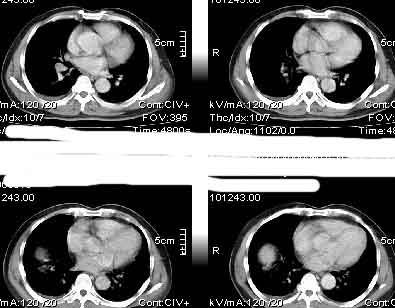

该病例我的诊断意见:右肺上叶周围型肺癌伴纵隔和右肺门淋巴结增大和右肺上叶阻塞性肺炎{病灶周围致密影以近肺门侧明显!}。右侧少量胸腔积液。

一. 1)症状有无发热及慢性过程.2)化验室检查?3)有无tb接触史?二.右肺上叶见片团状影,边界欠清,外侧方见一结节状软组织影,密度欠均匀,内可见低密度坏死区.周围强化明显,肺内见纤维索条影,局部胸膜增厚,但无明确胸膜凹陷.上叶支气管壁增厚,肺门及纵隔淋巴结增大.右侧胸腔少量积液.诊断意见:1右肺上叶慢性感染性疾病(肺tb?)伴肺门,纵隔淋巴结大.右胸少量积液.右肺上叶结节影多为tb球?2右肺上叶周围型肺ca伴肺门,纵隔淋巴结转移待排.右肺上叶炎变(肺门及纵隔淋巴结压迫).右胸少量积液.等待随返结果.

中轴间质增粗可以用癌局部淋巴侵润解释。近肺门侧片影用肺门淋巴结增大解释并压迫支气管引起近端炎症?